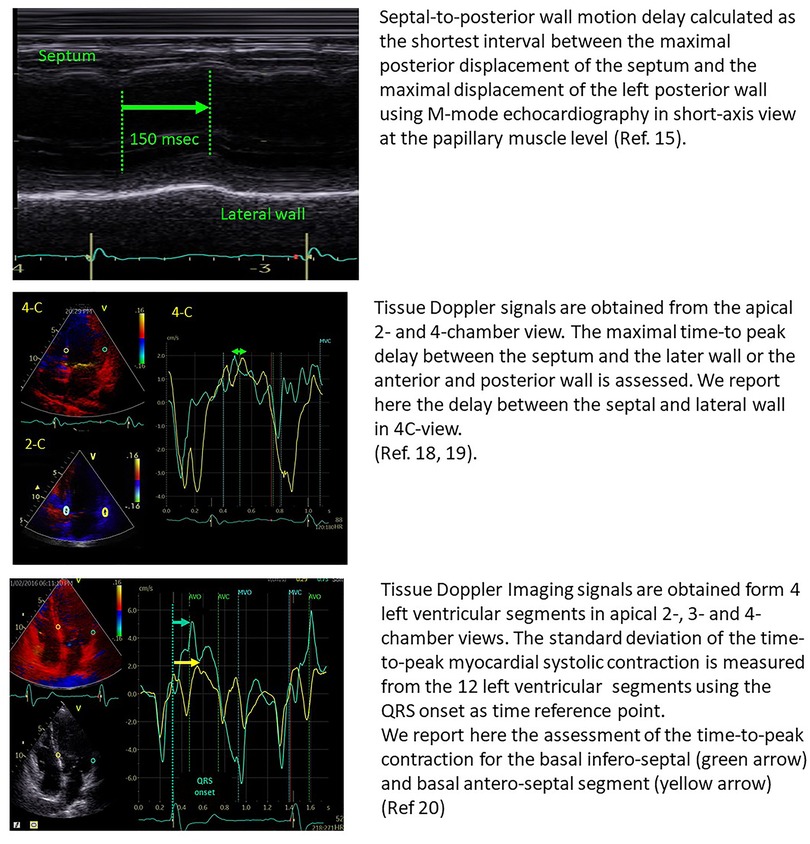

In 24 patients with heart failure, Pitzalis et al. showed that a septal-to-posterior motion delay ≥130 msec was able to predict LV reverse remodelling, with a positive predictive value of 80% and an accuracy of 85% (15). However, this approach was not suitable for patients with previous anterior or septal infarction and was plagued by poor temporal resolution (16). Successive studies, therefore, focused on tissue Doppler imaging and speckle tracking echocardiography for the assessment of LV dyssynchrony, by the estimation of opposite wall delay (17), or by focusing on the difference in peak systolic velocities of different myocardial regions (18–20) (Figure 1). Despite all these studies being able to show the good performance of echo-derived parameters for the prediction of CRT response in small, retrospective cohorts, the multicentric PROSPECT trial did not confirm the applicability of echocardiographic measures of dyssynchrony for the selection of CRT candidates (2).

Figure 1. Examples of the estimation of opposite wall delay in CRT candidates according to the main methods described in the literature. Upper panel: Pitzalis’ method; Middle panel: Bax's method; Lower panel: Yu's method.